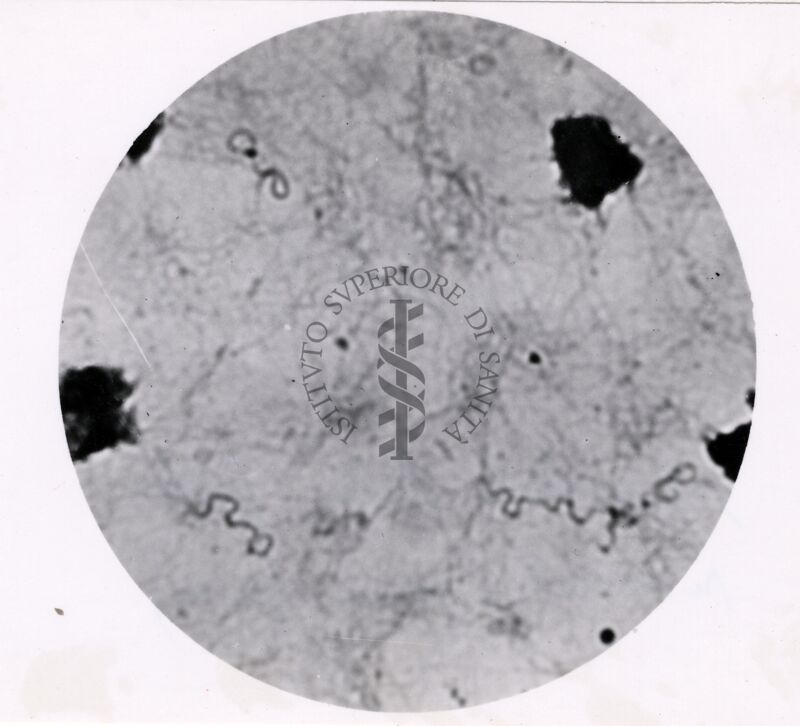

Spirochete della febbre ricorrente (gonia spessa)